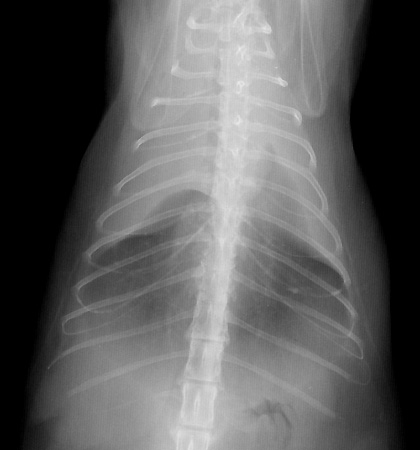

Radiograph of the Ventrodorsal view

Figure 2: Ventrodorsal view